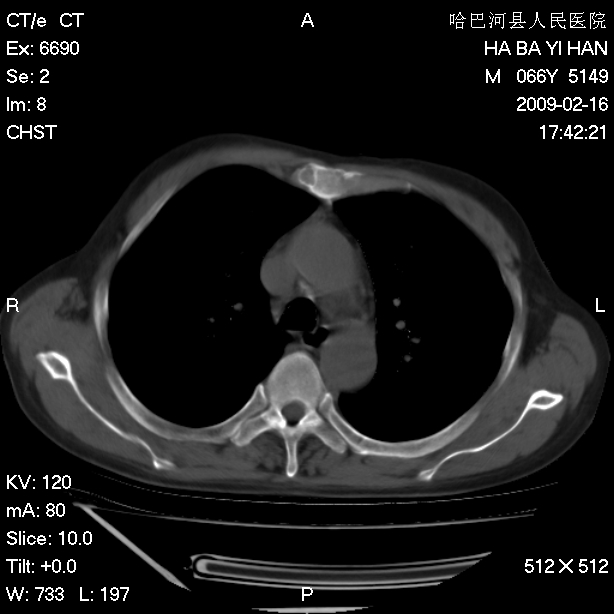

以下是引用huangxun4321在2009-2-16 20:18:00的发言:[br]部分病灶可见硬化边,部分可见骨质破坏消失,部分病灶内可见骨脊,说明病灶内既有良性病变,又有恶性病变,考虑骨巨细胞瘤恶变,未除骨纤恶变,畸形性骨炎少见,亦要考虑.

以下是引用731208在2009-2-16 20:31:00的发言:[br]考虑恶性胸膜间皮瘤并肋骨,脊柱转移。

以下是引用yijiansheng在2009-2-16 20:16:00的发言:[br]考虑恶性胸膜间皮瘤并肋骨,脊柱转移。

以下是引用形影不离在2009-2-16 19:55:00的发言:[br]考虑多发性转移瘤。